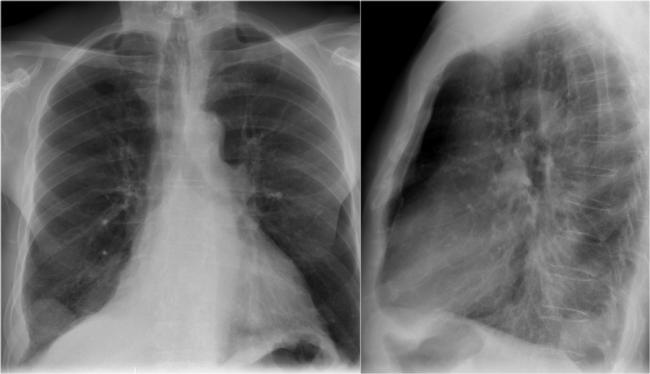

Помимо опроса и объективного осмотра, включающего перкуссию и аускультацию грудной клетки, проводят рентгенологическое исследование в двух положениях тела (в 2-х проекциях). Это основной метод обнаружения ателектазов легких.

На рентгеновских снимках выявляют следующие признаки, указывающие на спадение легочной ткани:

Однородное затемнение в области поражения. Размеры тени зависят от вида ателектаза: при долевом выявляется обширное затемнение, при сегментарном — в виде клина или треугольника, расположенного вершиной к корню легкого, дольковые ателектазы множественные и похожи на очаговую пневмонию. Дистензионный ателектаз расположен низко, около диафрагмы, имеет небольшие размеры и вид поперечных полос или темных дисков. Смещение органов: при компрессионном ателектазе смещение наблюдается в здоровую сторону, так как на стороне поражения давление больше, при обтурационном, наоборот – смещение будет в сторону ателектаза, так как на стороне поражения нарастает притягивающее отрицательное давление. Подъем купола диафрагмы – это видно по расположению печени.

Помимо всего перечисленного выше, рентгеноскопия, то есть исследование «вживую», позволяет увидеть куда смещаются органы в зависимости от фазы дыхания, кашля. Это является дополнительным признаком ателектаза, помогающим выявить тип болезни.

Если диагноз непонятен, рентгенологическое обследование дополняют компьютерной томографией. При перекрытии просвета бронхов выполняют бронхоскопию – осмотр по ходу бронхов с помощью зонда с камерой, который вводят в дыхательные пути.

Во время инструментальных диагностических манипуляций важно не только установить наличие ателектаза и его точную локализацию, но и уточнить объем спавшейся ткани, чтобы определить правильную тактику лечения и объем лечебных манипуляций. На рентгенограмме для диагностики ателектаза имеет значение состояние не только ткани легких, но и корней легких, ребер, органов средостения, купола диафрагмы, плевры, плевральной полости и даже позвоночника (будет наблюдаться его сколиотическое отклонение в направлении выпуклости в сторону пораженного легкого)

На рентгенограмме для диагностики ателектаза имеет значение состояние не только ткани легких, но и корней легких, ребер, органов средостения, купола диафрагмы, плевры, плевральной полости и даже позвоночника (будет наблюдаться его сколиотическое отклонение в направлении выпуклости в сторону пораженного легкого).